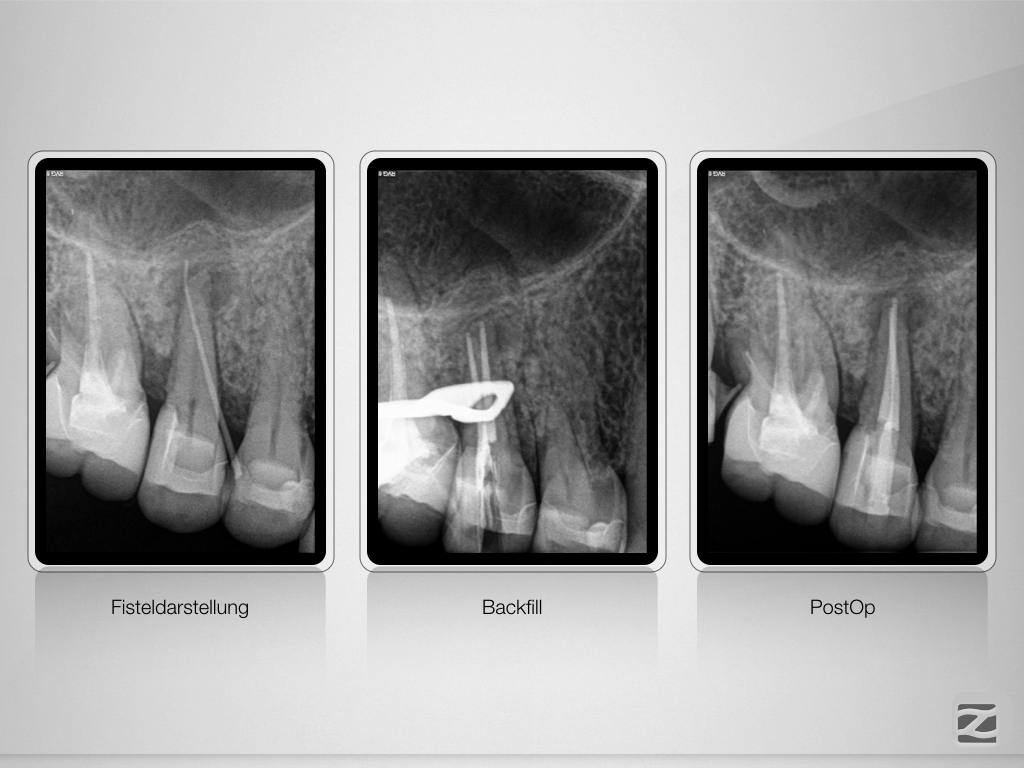

Wie weit ist weit genug?